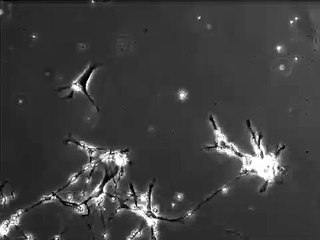

Neuron Function